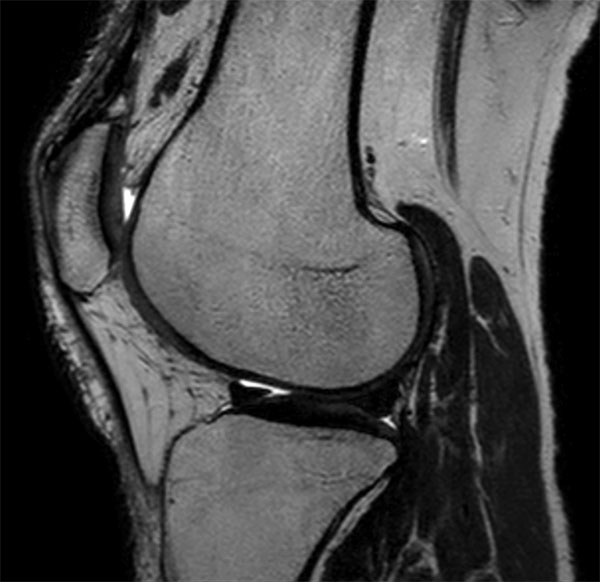

Comprehensive 3D knee imaging with MSK VIEW